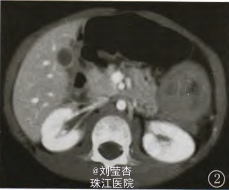

查体:腹软,左侧腹部局部压痛,无反跳痛,余查体未见异常。辅查:胸腹部CT:降结肠内见突入腔内的软组织块影,直径约3.3cm,增强后明显强化。行无痛肠镜检查:降结肠近脾曲处见突入腔内的肿块影,直径约3cm,肿块表面充血、水肿、糜烂伴溃疡形成,管腔狭窄,内镜勉强通过,考虑为降结肠癌。镜下取组织行病理检查,提示为少量纤维、脂肪组织,其间见少量淋巴细胞浸润。